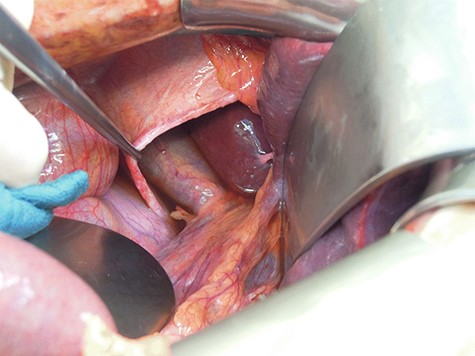

Intraoperatively, the defect could be closed by direct single stitch suture using a non-resorbable, braided thread, reinforced with a Parietene composite® mesh (Figs 3 and 4), a macroporous polypropylene mesh covered with an absorbable synthetic film. Further abdominal inspection was inconspicuous. Tension-free closure of the abdomen was performed. Event-free extubation postoperatively, the standard postoperative X-ray after intraoperative chest tube placement was unremarkable.